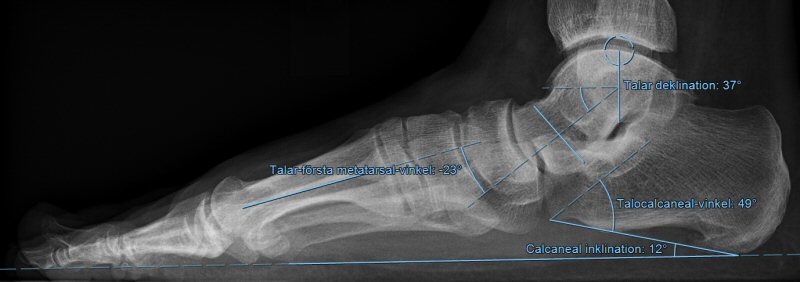

Meary’s vinkel (vinkel mellan talus längsaxel och metatarsale 1):

- -4° - +4 °: normalt

- 4-15° : mild plattfot

- 15-30°: måttlig plattfot

- > 30°: svår plattfot

Exempel på måttlig plattfot. Klicka på bilden för förstoring.